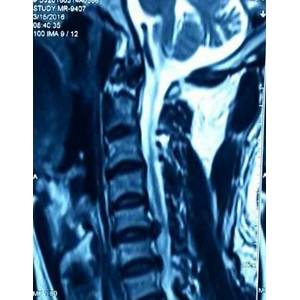

巨大颈椎椎间盘突出一例典型病例分享

患者:秦**,男,53岁 籍贯:周口, 住院号:268**7, 住院日期:2016/3/13 主诉:项背部及右上肢放射性疼痛1周 现病史:1周前劳累后突然出现项背部及右上肢持续性剧烈疼痛,伴有右手食指、中指麻木、憋胀感,上举 ...